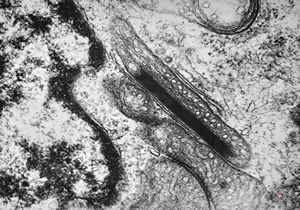

M,26y. | ribosome-lamella bodies in adenocarcinoma

M,41y. | ribosome-lamella complex in tricholeukocyte -hairy cell leukemia, spleen